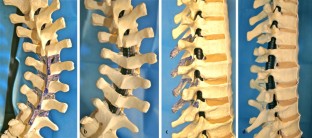

Abb. 3